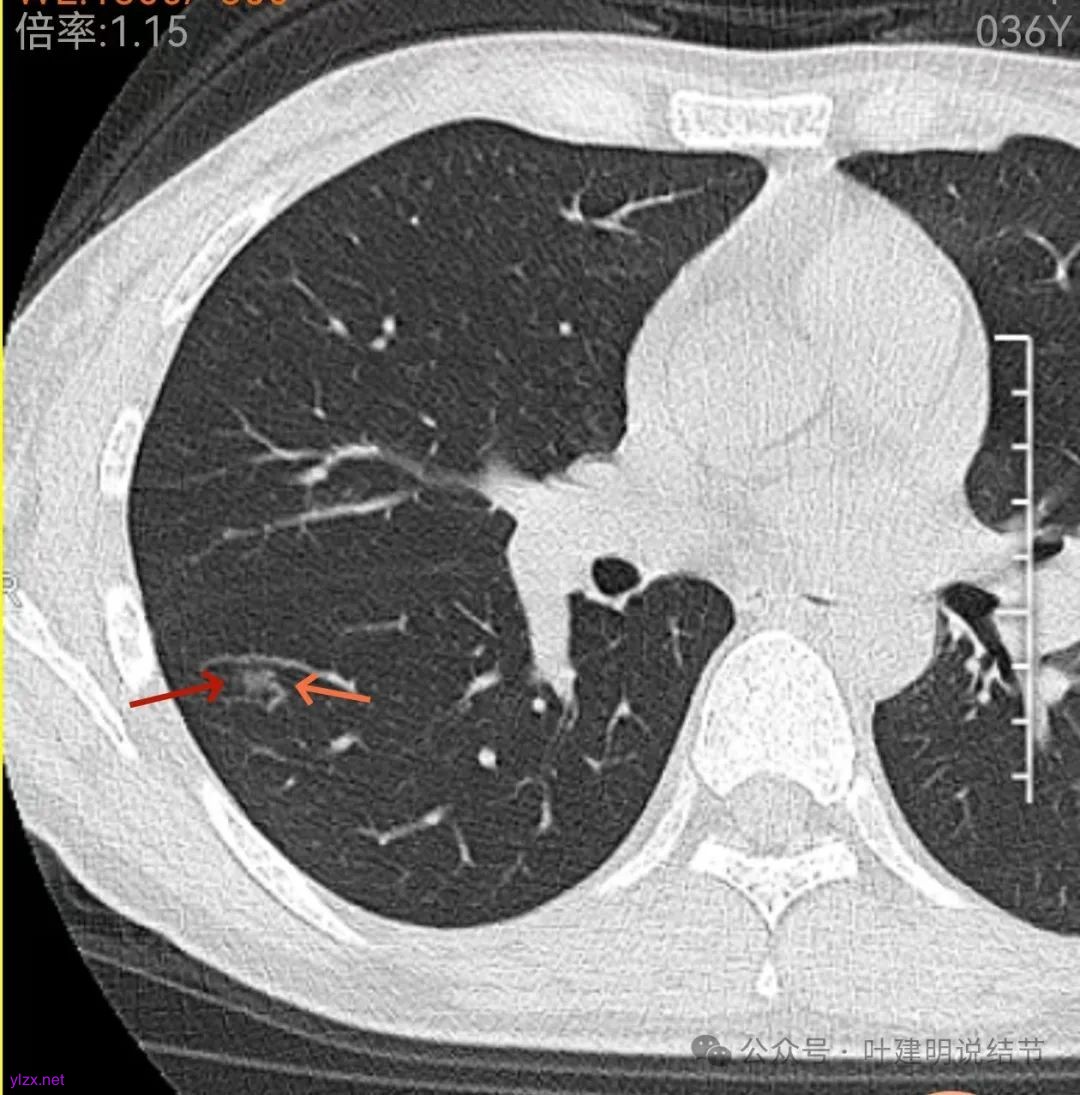

再看中间2023年的影像:

右下此灶2023年时此层面淡而边显糊。

上图层面已经像混合密度了,表面毛糙不光滑,灶内密度不均,也有小空泡征的样子。

感觉这处(在上截图结节的下面点,邻近层面)不像前面病灶的延伸,否则这密度的变化有点突兀呀。

两肺多发结节,左侧黄色标注的考虑是肺泡上皮增生可能性大;蓝色的考虑肺泡上皮增生或者少许慢性炎可能性大;右侧红色宽起来并带有红色箭头的这处是主病灶,偏混合密度,整体轮廓较为清楚,边缘显得毛糙,从2024年12月份的来看,要考虑是肿瘤范畴,原位癌或者微浸润性腺癌可能性较大,也不能完全排除不典型增生。但是在2022年的时候,这个病灶的边上也有一个实性的微小结节,如果只看2022年的,这么小的实性结节,又比较圆,表面也显得较为光滑,是要考虑良性的,当然太小了需要动态观察。回头再重新来看2024年底的,发现绿色箭头所指的这个微小实性的较2022年几乎没有变,去仔细寻找2022年的,发现当时在实性结节旁边也有密度很淡的一点磨玻璃影(也可能真的就是一处,只是扫描不够薄,密度的变化有些突兀而已),而到了2024年12月份,实性微小这处没有明显变化,但是原来很淡的磨玻璃变成了混合磨玻璃,范围也明显扩大。所以总体来看右肺下叶这处是考虑恶性的,而且从磨玻璃结节角度来讲,还是生长比较快的,就是说还是有一定风险的。加上左侧还有两处也是磨玻璃持续存在,虽然边缘轮廓显模糊一点,但多年以后也可能仍然要变成原位癌或者微浸润性腺癌之类的东西。通盘考虑以后,我倾向于右侧近期单孔胸腔镜下微创局部切除,左侧随访观察,等到有进展并风险增加再来考虑处理。意见供参考!